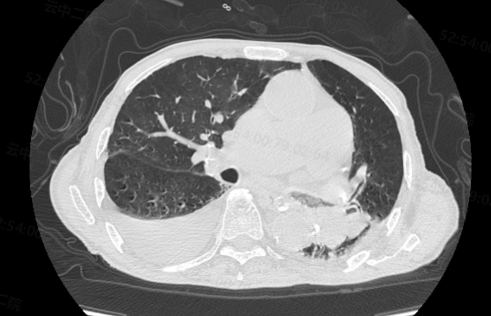

就诊前,患者出现持续高热,咳嗽、喘息,经皮血氧饱和度持续面罩吸氧下88%左右,积极完善相关检查,动脉血气分析提示II型呼吸衰竭。血常规提示细菌感染。脑钠肽升高。【胸部CT】提示:双侧胸腔积液,左舌叶及左下叶分支气管内痰栓形成。情况十分危急。夏世金博士后团队详细查看患者资料,分析病情后,建议先行支气管镜检查,明确肺部感染情况。

胸部CT:左主支气管痰栓形成